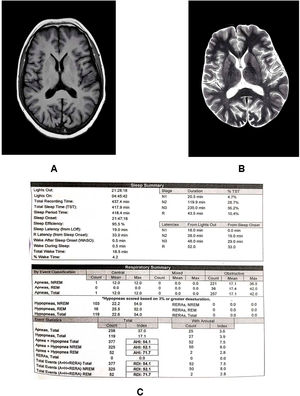

A non-contrast brain computed tomography and a brain MRI revealed mild frontoparietal cortical atrophy and bilateral mild focal periventricular leukomalacia without any evidence of acute ischemic or hemorrhagic stroke (Fig. 2A and B).

Epworth sleepiness scale reading was 13/24 (moderate excessive daytime symptoms). On performing polysomnography for 538 min, both apnea–hypopnea and respiratory disturbance indexes were found to be 44.3 and oxygen desaturation index of 31.7/h, respectively, with a minimum oxygen saturation of 63% (Fig. 2C). Upon discharge, he was initiated on a low-dose prophylactic oral levetiracetam (500 mg twice daily) for 6 months and maintenance of continuous positive airway pressure during sleep with closed follow-up. Levetiracetam was then withdrawn. The patient remained asymptomatic and seizure-free 1 year after discharge, with an improved Epworth sleepiness score.